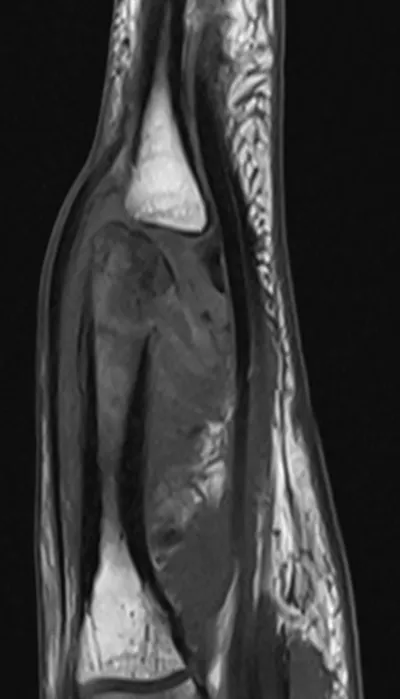

Osteomyelitis Radiology Images

About Osteomyelitis Imaging

This collection contains 2 radiology images related to osteomyelitis, including various imaging modalities such as X-rays, MRIs, CT scans, and ultrasound images commonly used in medical diagnosis and education.